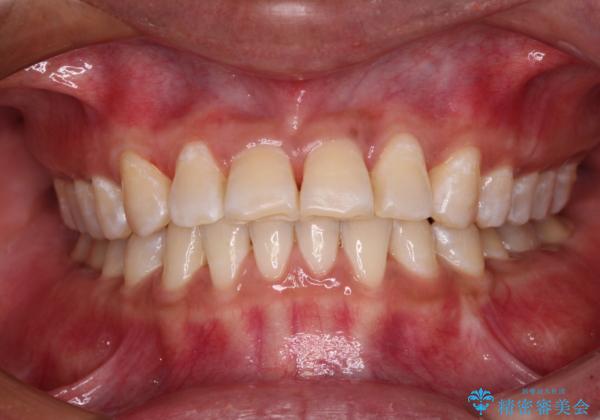

反対咬合の改善 途中で出産をしながらワイヤー矯正

- 前歯の隙間と反対咬合を気にして来院された患者様です。

咬合力が強く、反対咬合の改善に時間がかかりましたが、その後はスムーズに進めることができました。